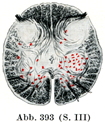

[図381]脊髄の横断模型図 柔膜および歯状靱帯をつけてある. 神経細胞は赤で示す.

灰白質がそこから出る神経根に比例して増加あるいは減少することは上に述べた.しかしこのことはまず第1に前柱に関連しているのである.後柱は膨大部のために影響されることが比較的に少い.もっとも後柱の膨らみがそこで増すことは確かである.このことは特に腰膨大であてはまるのであって,ここでは後柱がかなり大きな幅をもっている.頚膨大における前柱の増加は,まず側方に増大するので孤立した側柱はもはや見られなくなる.脊髄円錐の尖端に向かっては前柱と後柱との境がなくなる.同時に両側の後柱はますます近より,結局合して一塊となる.